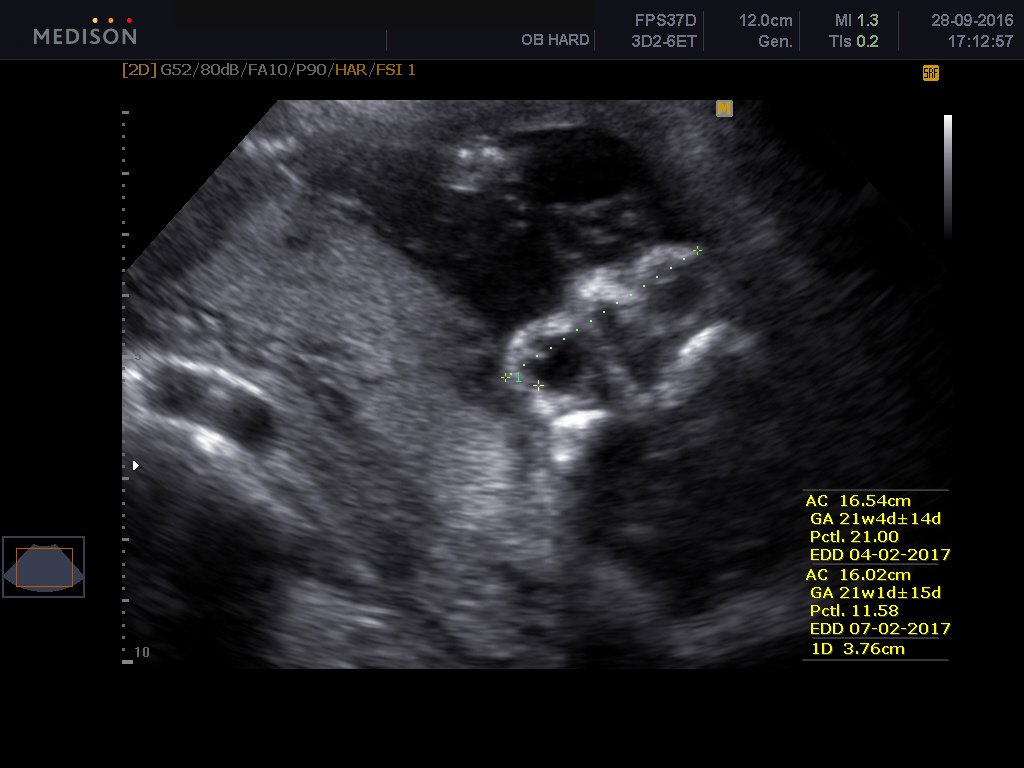

To υπερηχογράφημα β επιπέδου είναι ειδικό υπερηχογράφημα το οποίο εκτελείται από εξειδικευμένο ιατρό και με το οποίο ελέγχεται λεπτομερώς η ανατομία του εμβρύου. Γίνεται όπως όλα τα υπερηχογραφήματα δια μέσου της κοιλιακής χώρας της εγκύου και είναι απόλυτα ανώδυνο.Είναι δυνατόν το υπερηχογράφημα να απεικονίσει σοβαρές συγγενείς ανωμαλίες του εμβρύου καθώς και ελαφρές ανατομικές βλάβες. Επίσης αναγνωρίζει υπερηχογραφικά σημάδια , τα καλούμενα markers , με τα οποία υποπτευόμαστε σοβαρά χρωμοσωμιακά σύνδρομα εμβρύου, όπως το σύνδρομο Down, την trisomy 18 και trisomy 13. Γίνεται έλεγχος του πλακούντα εκτιμάται το αμνιακό υγρό καθώς και η προβολή του εμβρύου και ο τράχηλος της μήτρας και ειδικά το μήκος τραχήλου μας δίνει πληροφορίες όσον αφορούν τον πρόωρο τοκετό.

Ελέγχεται το κρανίο, ο εγκέφαλος, το πρόσωπο, η καρδιά, τα χέρια, τα πόδια, η σπονδυλική στήλη, η ουροδόχος κύστη του μωρού. Μερικές συγγενείς βλάβες που μπορεί να αναγνωρίσει το υπερηχογράφημα είναι οι εξής: Ανεγκεφαλία, ανοιχτές βλάβες νωτιαίου σωλήνα , χειλεοσχιστία -λαγόχειλος, διαφραγματοκήλη, γαστρόσχιση , εξόμφαλος, σοβαρές καρδιακές συγγενείς ανωμαλίες, αγενεσία νεφρών, πολυκυστικούς δυσπλαστικούς νεφρούς, θνησιγενείς σκελετικές δυσπλασίες.

Σύμφωνα με πανευρωπαϊκή στατιστική μελέτη η υπερηχογραφική δυνατότητα ανίχνευσης σοβαρών συγγενών ανωμαλιών ανέρχεται στο 73,7%, ενώ των ελαφρών συγγενών ανωμαλιών στο 45,7%. Υπερηχογραφικά μόνο δεν είναι δυνατόν να αποκλεισθεί η πιθανότητα χρωμοσωμιακής ανωμαλίας καθώς και όλων των συγγενών ανωμαλιών.